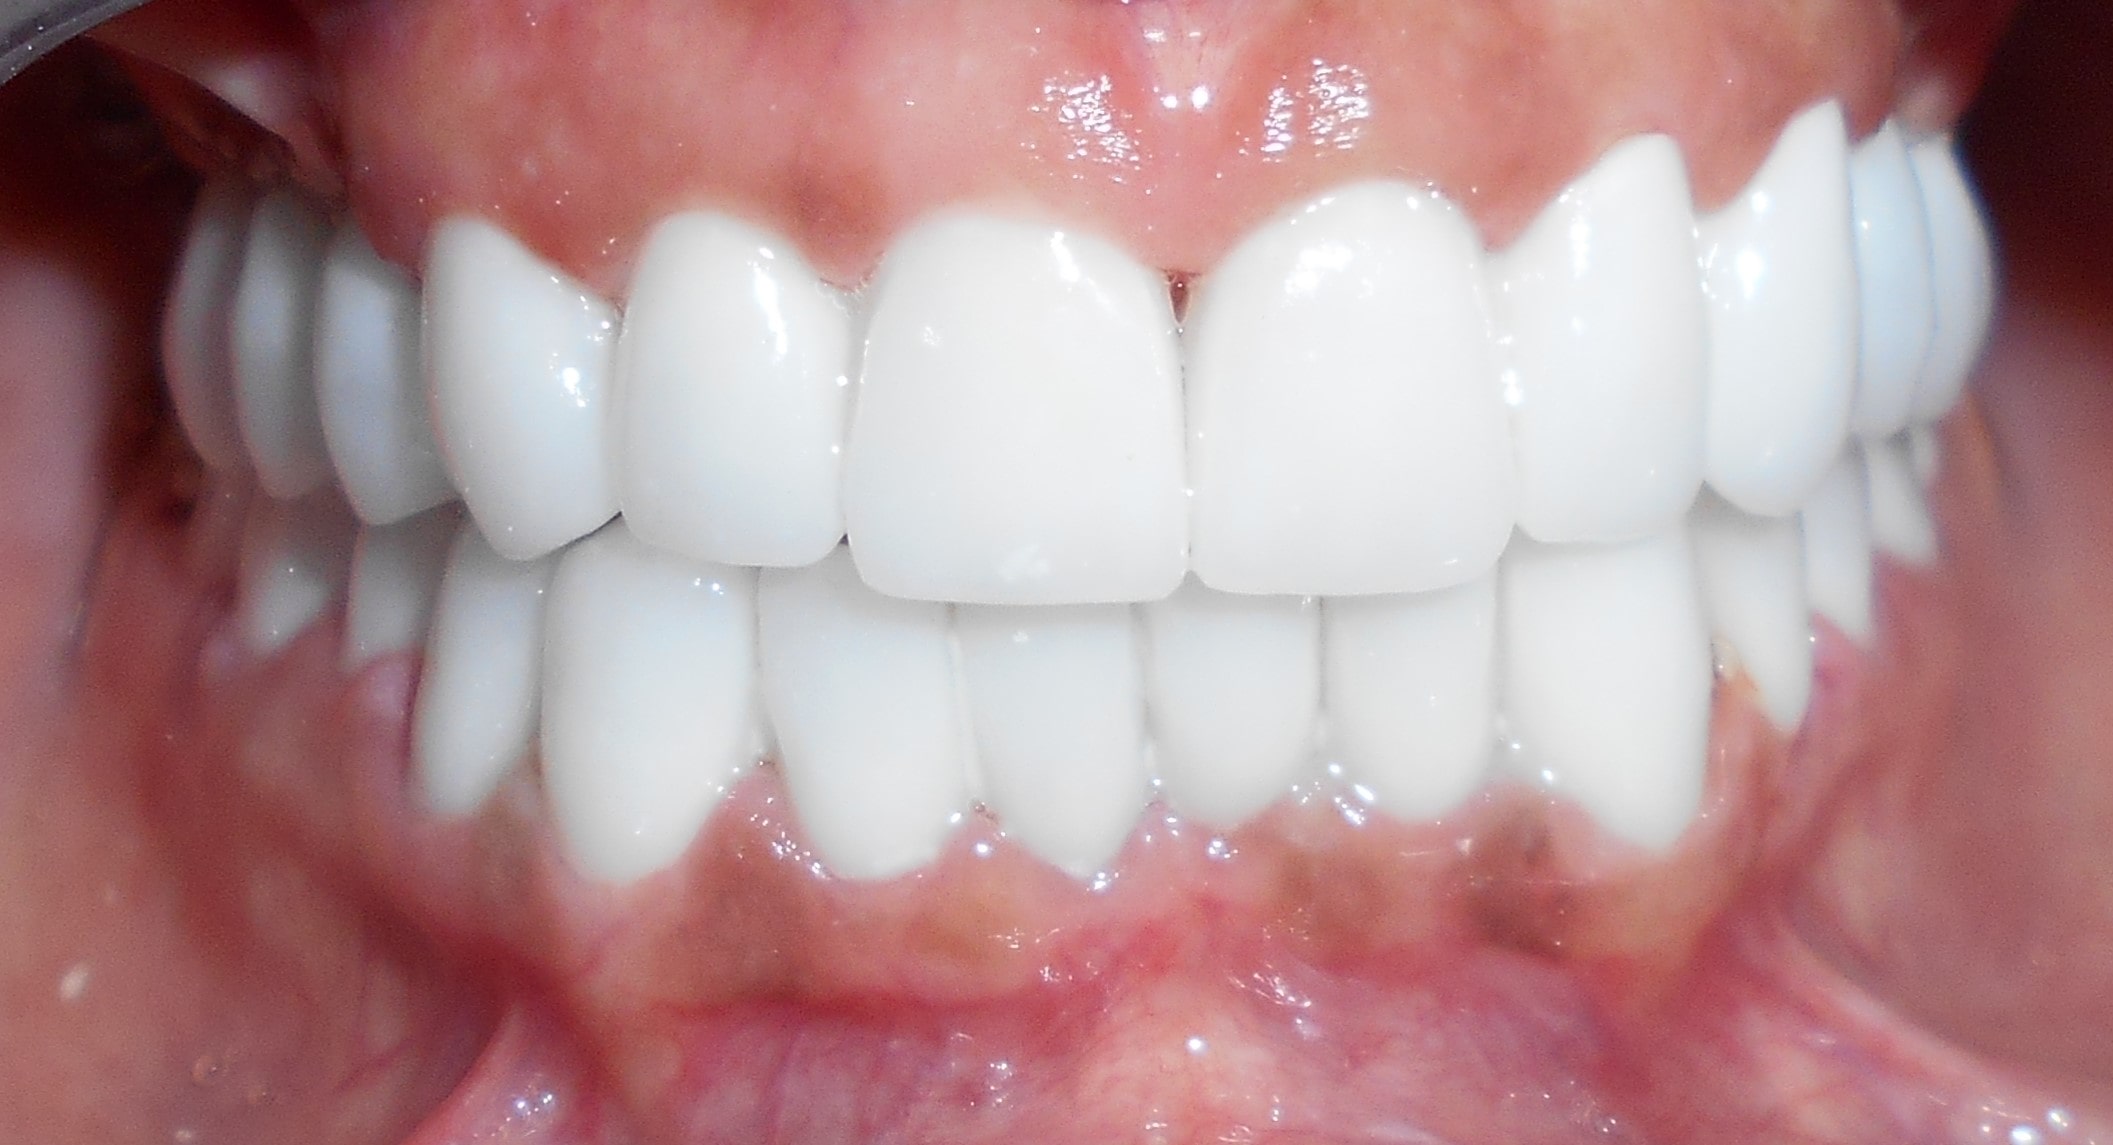

Pacijent 1

Pacijent iz Nemačke, kod koga smo estetsko i funkcionalno zbrinjavanje rešili cirkonijum keramičkim krunicama sa ugradnjom kratkih implantata u donjoj vilici zbog smanjene visine kosti, a u gornjoj vilici na levoj strani odmah nakon vađenja zuba je ugrađen standardni implantata na mesto izvađenog zuba i ugrađen je tuberopterigoidni implantat da se ne bi radila komplikovana sinus lift procedura koja bi produžila vreme završetka rada na godinu i više dana. Rad uspešno završen i pacijent nema nikakvih problema već pet godina.

Pacijent 2

Pacijent sa obe strane gornje vilice je bio bezub, sa minimalnom horizonatlnom i vertikalnom visinom kosti kao i sa spuštenim sinusom. Nakon dužeg traženja rešenja za svoj slučaj u drugim ordinacijama da bi izbegao komplikovanu sinus lift proceduru prihvatio je naš predlog da se ugrade po tri implantata sa obe strane gornje vilice od kojih su dva tuperopterigoidna implanta, koji su rešili problem spuštenog sinuasa sa minimalnom traumom prilikom ugradnje. Slučaj rađen pre četiri godine. Na poslednjoj kontroli izgleda besprekorno.

Pacijent 3

Pacijent dolazi sa starim mostovima i izraženom parodontopatijom u donjoj vilici. Urađeno je skidanje postojećih mostova i istovremena ekstrakcija svih parodontopatičhin zuba uz ugradnju sedam implantata u gornjoj vilici i pet implantata u donjoj vilici. Pacijent je nakon tri dana bio privremneo protetski zbrinut sa fiksnim privremeni krunicama koje su fiksirane na tek ugrađenim implantaima. Nakon četiri meseca je izrađen fiksni cirkonijum kermički- bezmetalni most u gornjoj i donjoj vilici. Rad uspešno završen pre tri godine.

Pacijent 4

Pacijent iz inostranstva doalzi sa totalnom protezom u gornjoj vilici i sa uznapredovalom parodontopatijom preostalih zuba u donjoj vilici. Pacijent navodi da su mu u inostranstvu rekli da je nemoguće u gornjoj vilici ugraditi implantate bez velikih hirurških zahvata koji podrazumevaju transplantaciju kosti sa udaljenih delova tela i sinus lift proceduru. U gronjoj vilici je bila minimalna količina kosti sa izraženo spuštenim sinusima i sa minimalno vretikalnom i horizontalnom visinom kosti. Naše rešenje se sastojalo u sledećem: ugradnja deset implantata u gornjoj vilici u raspoloživu kost sa ugrdnjom veće količine veštačke kosti, od deset ugrađenih implanta dva implantata su tuberopterigoidna koji su zamenili sinus lift proceduru. U gornjoj vilici smo se opredelili za ugradnju većeg broja implantata kako bi prilikom izrade fiksnog protetskog rada dobili ravnomeran prenos pritiska žvakanja na implantate. U donjoj vilici intervencija je bila istovremena i ona je podrzumevala vađenje svih preostalih zuba i ugradnju osam implantata. Kompletno zbrinjavanje koje obuhvata hiruršku i protetsku fazu je trajalo tri meseca, tokom kojih je pacijent u gornjoj vilici bio zbrinut sa privremenom totalnom protezom, a u donjoj vilici sa fiksnim privremenim zubima koji su bili fiksirani na tek ugrađenim implantatima. Definitivni protetski rad je uspešno završen sa cirkonijum keramičkim - bezmetalnim mostovim pre četiri godine.

Pacijent 5

Pacijent kod koga je rađena kombinacija rešavanja bezubih prostora sa ugradnjom implantata, a nakon tri meseca kompletno rešavanje sa cirkonijum keramičkim -bezmetalnim krunica i mostovima.